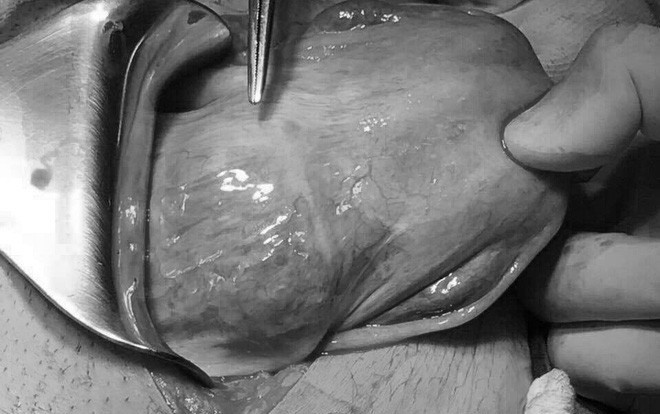

Cuộc phẫu thuật diễn ra với sự phối hợp của ekip các BS Sản phụ khoa, Niệu khoa, Gây mê hồi sức, Huyết học truyền máu… Sau 1 giờ 20 phút phẫu thuật, khối thai với đường kính 6cm được bóc trọn khỏi sẹo mổ cũ, khâu phục hồi sẹo mổ và bảo tồn được tử cung cho bệnh nhân. Quá trình phẫu thuật, bệnh nhân đã được truyền 2 khối hồng cầu trước mổ để ổn định tình trạng thiếu máu. Hiện chị Tr. đã không còn đau bụng, hết chảy máu và đang hồi phục tốt.

Ca phẫu thuật bóc tách khối thai bám sẹp mổ cũ kéo dài trong 80 phút.